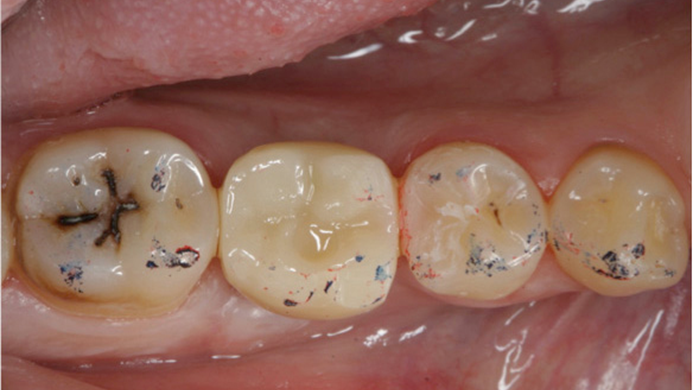

Clinical case: # 46 implant placement & GBR using i-Gen membrane for significant vertical resorption & mixed bone defect

AnyRidge, mandibular posterior, i-Gen, resorption, bone defect, bone regeneration, space management, #46, GBR, Dr. Iulian Filipov